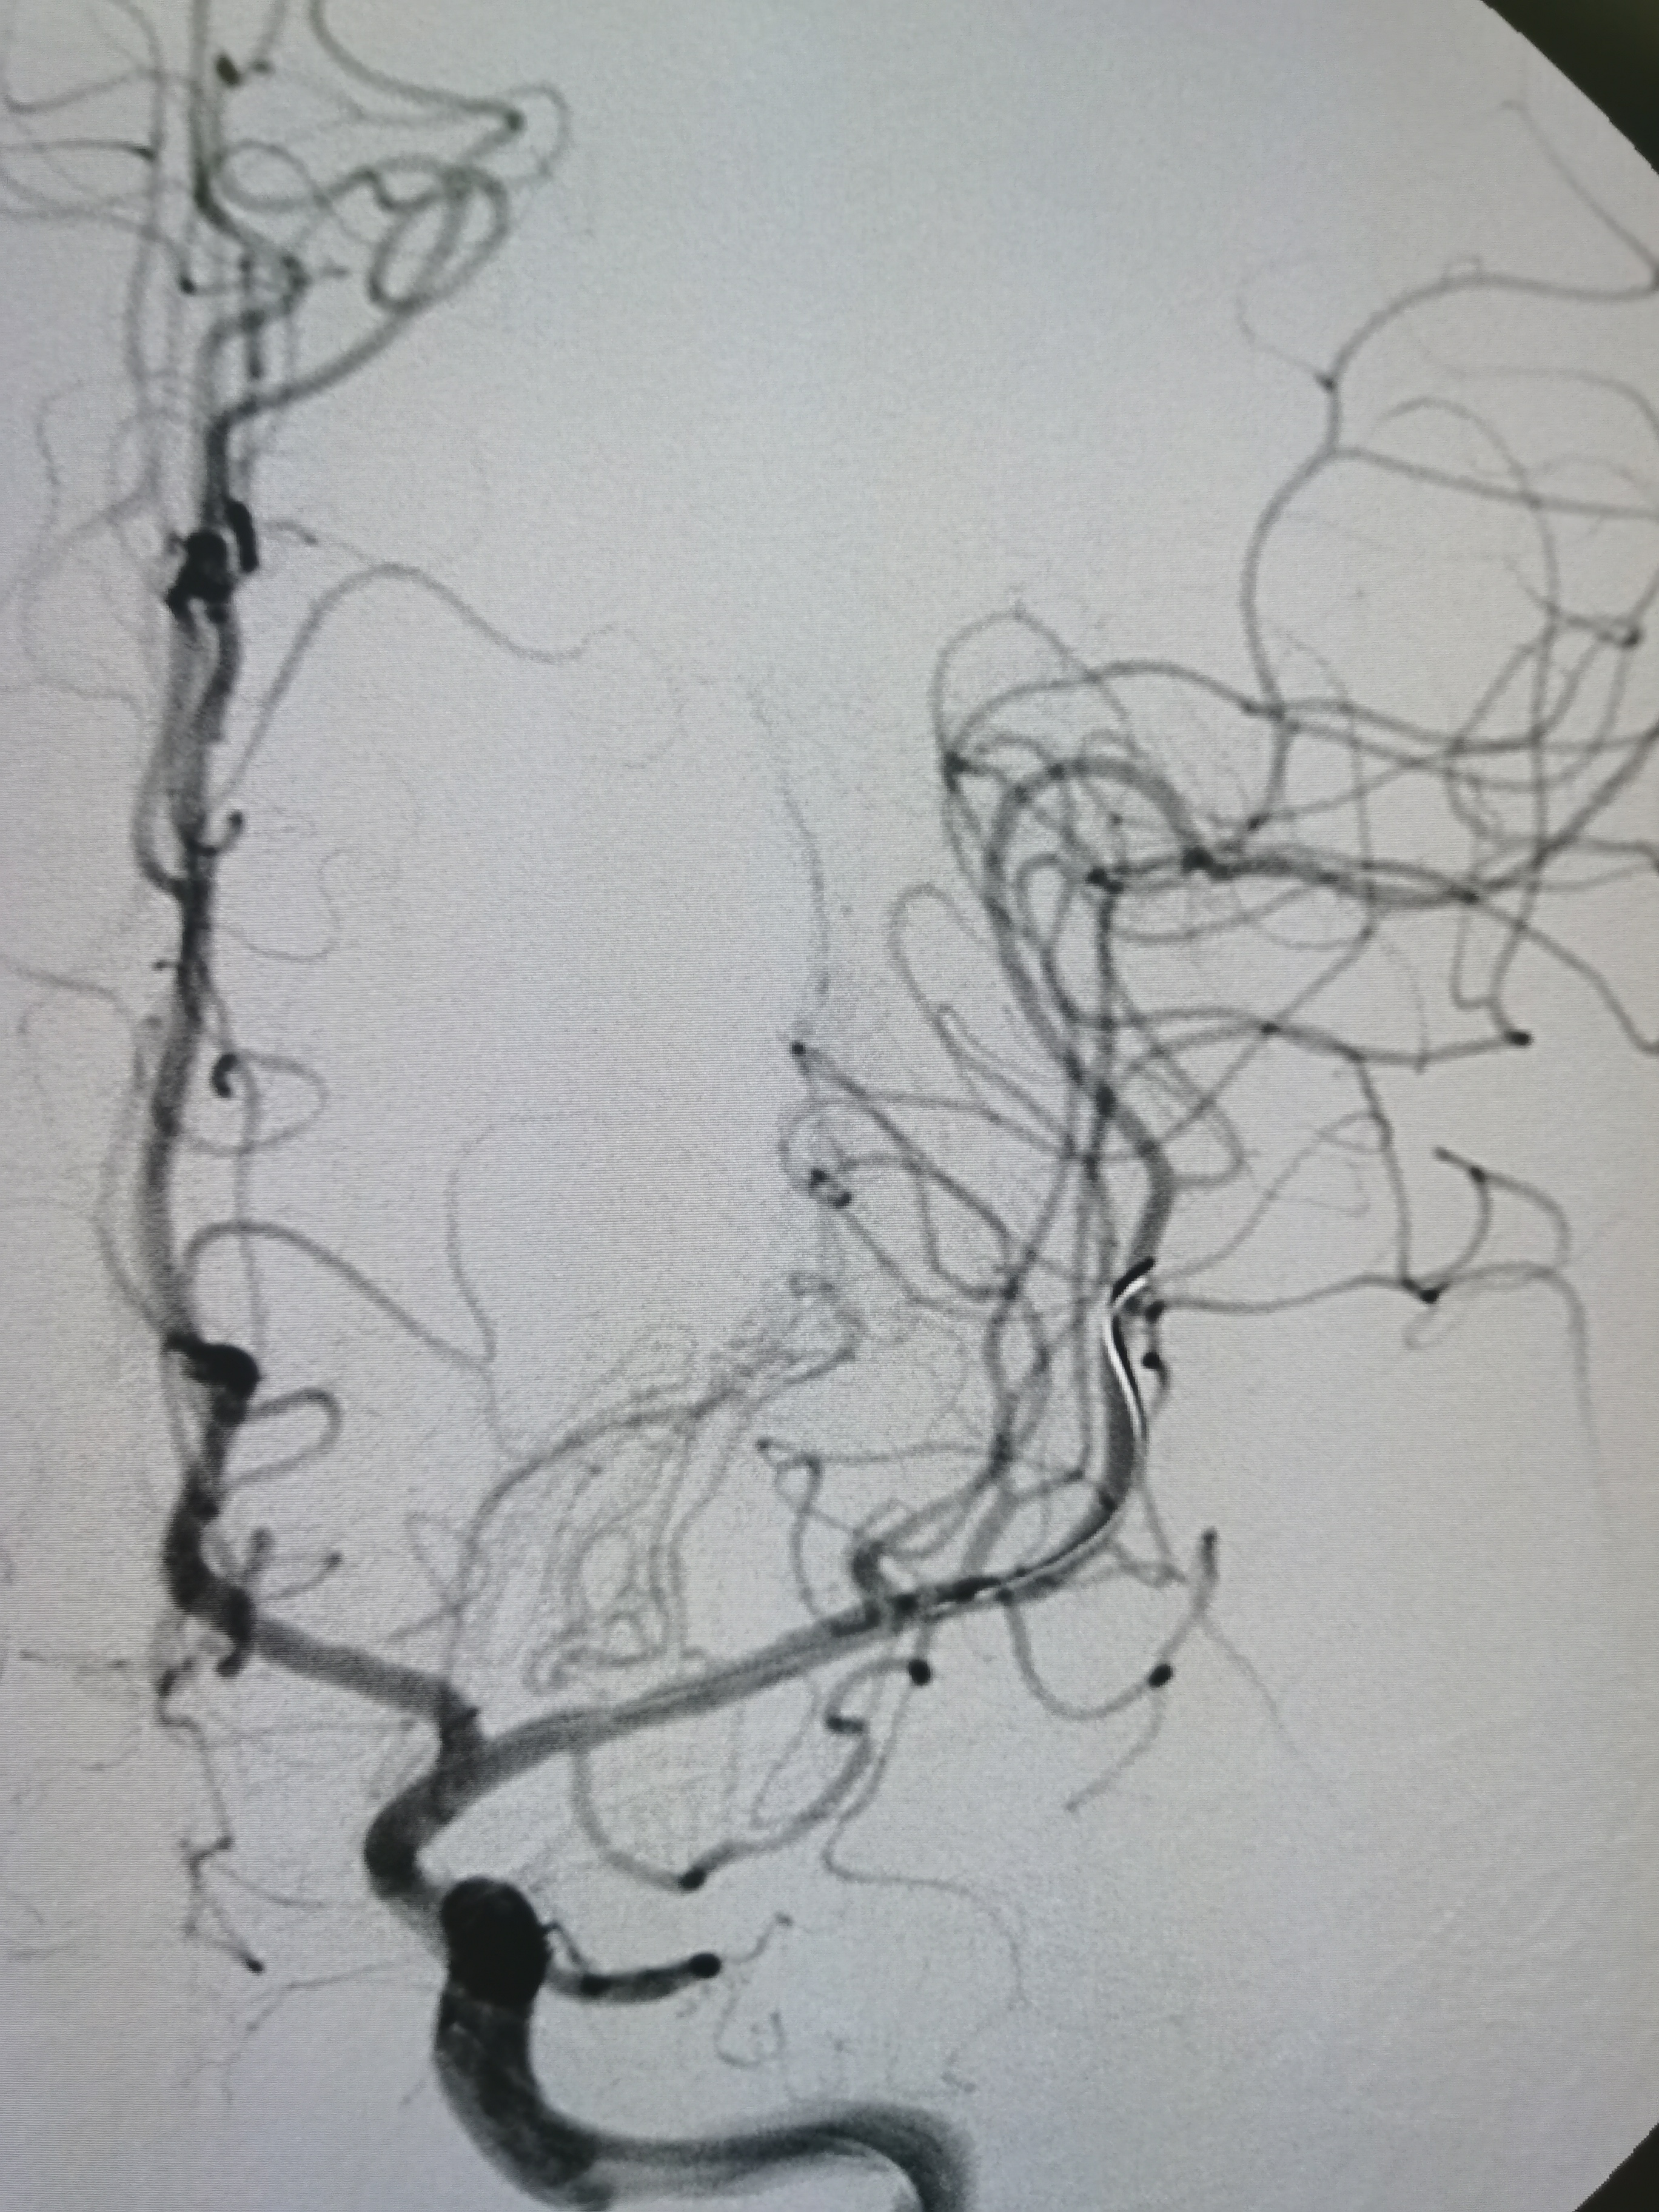

侧位见左侧大脑中动脉闭塞。

晚期可见左侧大脑中动脉返流。

正位见左侧大脑中动脉闭塞。

动脉晚期可见左侧大脑中动脉M2段返流。

造影分析:

患者左侧大脑中动脉M1起始段闭塞,动脉晚期可见返流至M2显影,考虑新近闭塞,具备介入开通指征,手术风险在于血管夹层,破裂及急性血栓形成,向患者家属详细交代病情后,家属积极要求介入治疗。